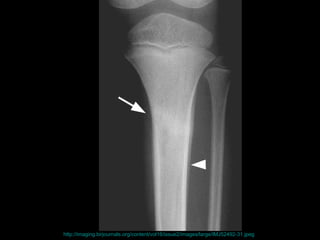

壓力性骨折 Stress Fracture 疲勞骨折 Fatigue fracture   骨質不良性骨折 Insufficiency fracture http://www.emedicine.com/radio/topic783.htm

http://imaging.birjournals.org/content/vol16/issue2/images/large/IMJ52492-31.jpeg

the failure of the skeleton to withstand submaximal forces over time.  the failure of the skeleton to withstand submaximal forces over time.  http://www.mypacs.net/repos/mpv3_repo/viz/full/17093/854689.jpg